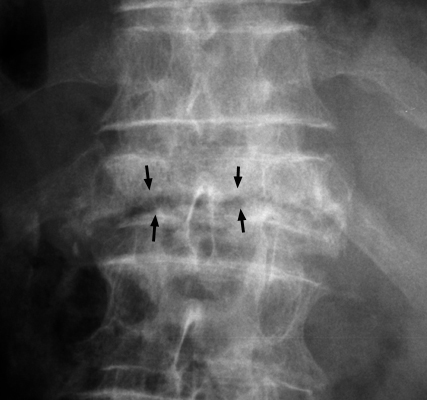

Single frontal radiograph of the spine revealing a horizontally oriented linear area of lucency within the body of a single collapsed vertebral body. The intravertebral vacuum cleft sign is a gas-density cleft with a transverse separation of the vertebral body, appearing in extension and disappearing in flexion. It is secondary to local bony ischemic necrosis with nonhealing vertebral collapse. This ischemic vertebral fracture is not known to occur secondary to inflammation or neoplastic causes.